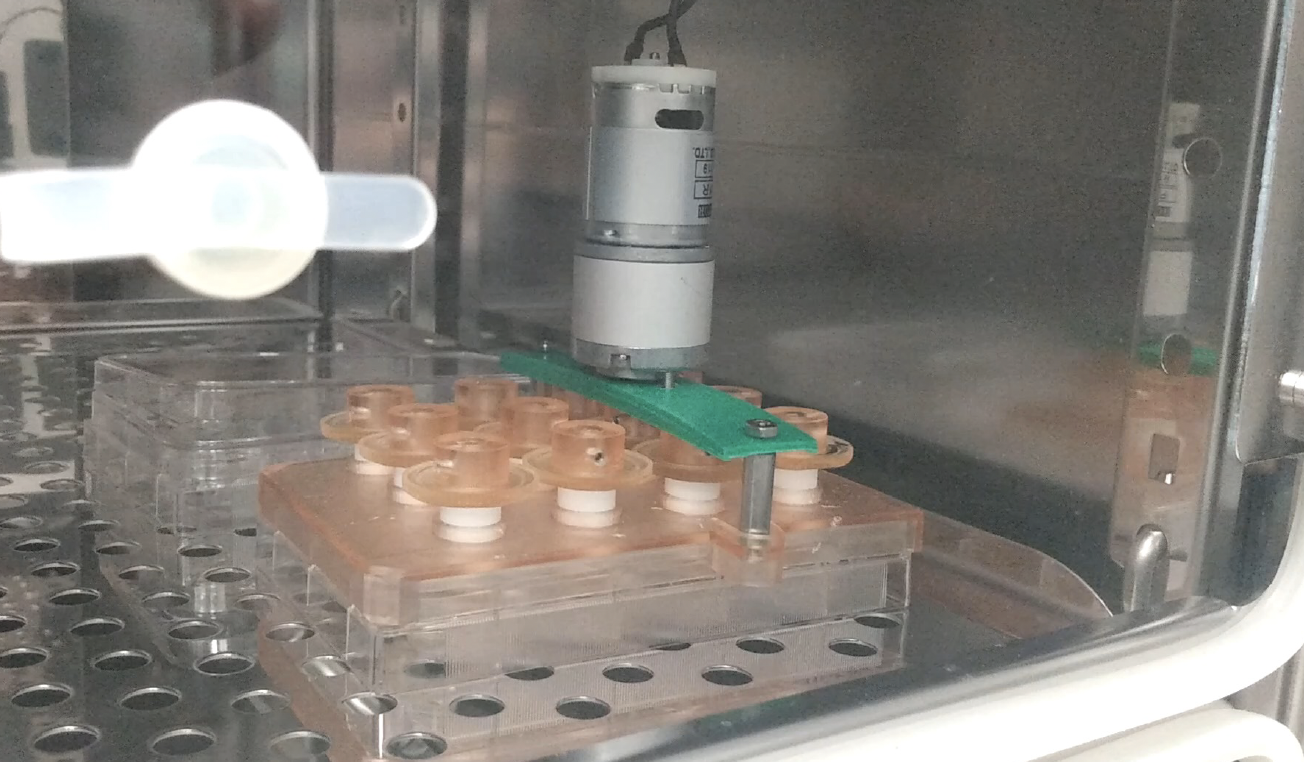

Masters work - validation of rotator cuff repair patch with stem cell implanted hydrogel.

Implanting cells into hydrogel and performing live/dead stain assay.

Assisted another lab in building 12-well plate bioreactors for organoid research.

Bioreactor grown canine organoids.